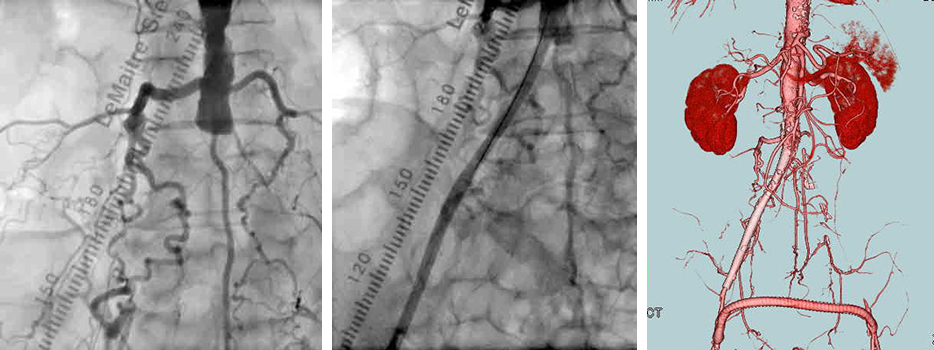

- 大動脈狭窄 【写真】

- 高位大動脈閉塞(Leriche synd) 【写真】

- 腸骨動脈完全閉塞(右) 【写真】

- 腸骨動脈狭窄 【写真】

考え方としては、早期であるほど2の血管内手術のみで治る可能性が高いと考えてよいでしょう。現在の末梢動脈に対する血管内手術の適応は、大動脈・腸骨動脈領域から膝下動脈、さらに足関節から足趾にまで及びます。しかし、それぞれの治療法には当然ながら適応があります。このためしばしば従来からの手術との組み合わせであるハイブリッド手術が必要になりますが、血管内呪術の関与する割合は8~9割にも及んでいます。